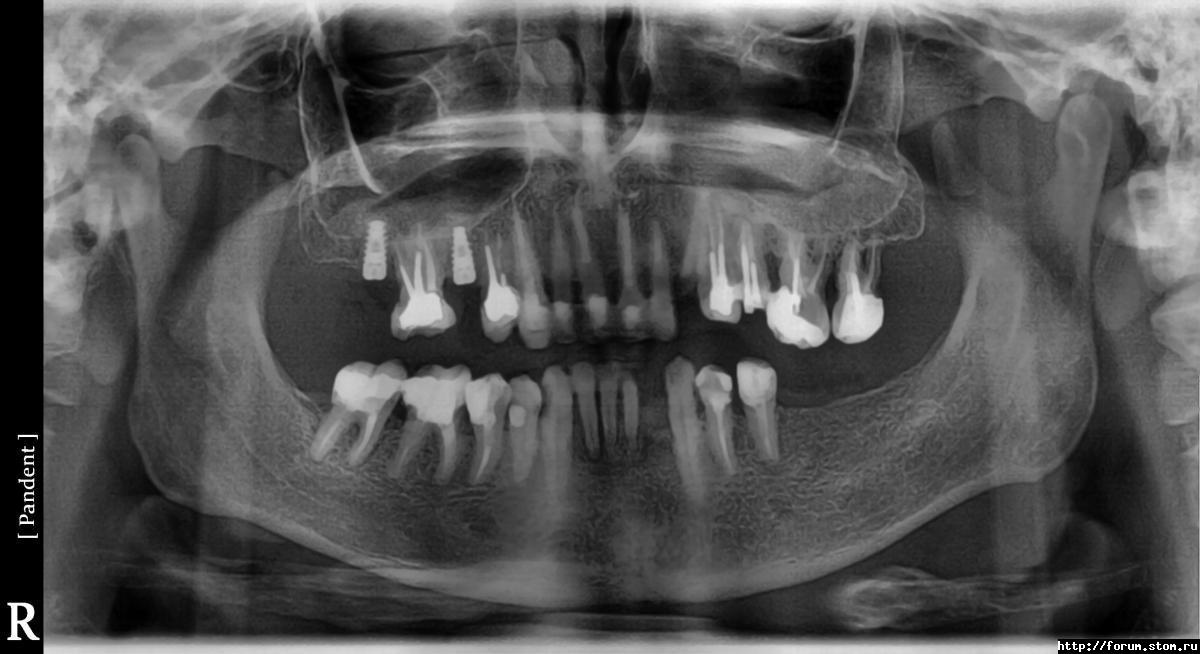

alexy78rus Опубликовано 7 ноября, 2011 Поделиться Опубликовано 7 ноября, 2011 Как, на Ваш взгляд, правильно или нет установленно два импланта? У этого врача предстоит устанавливать еще 5-7штук. По ощущениям - острая боль после проподания наркоза в течении 10часов. Далее небольшой отек и поднывания 7дней.Сегодня пойду снимать швы. Ссылка на комментарий

Большой Зеленый Опубликовано 7 ноября, 2011 Поделиться Опубликовано 7 ноября, 2011 Все хорошо Ссылка на комментарий